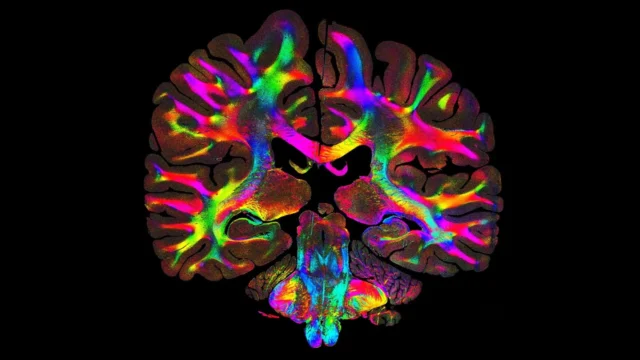

O método requer apenas uma luz LED rotativa e uma câmera de microscópio, tornando a configuração acessível em comparação com outras formas de microscopia avançada. Depois que as imagens são coletadas, o software analisa as amostras frágeis em luz espalhada para criar mapas codificados por cores de orientação e densidade das fibras, conhecidos como distribuições de orientação de fibras baseadas em microestrutura.

O principal objetivo da neurociência é definir as vias microscópicas do cérebro com alta precisão. Usando o ComSLI, Georgiadis e colegas criaram imagens de seções completas do cérebro humano fixadas em formalina e embebidas em parafina e lâminas de tamanho padrão, revelando estruturas detalhadas de fibras em todo o tecido.